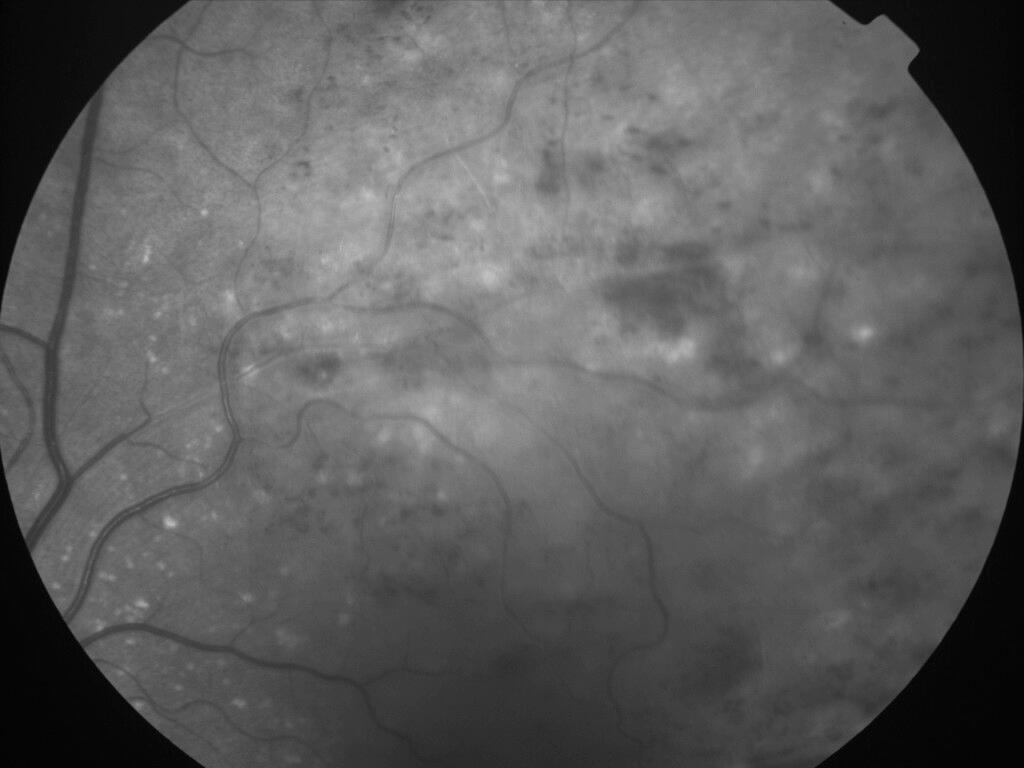

OCCLUSION DE BRANCHE DE LA VTS DE FORME ISCHEMIQUE MAJEURE